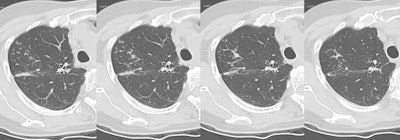

Reactivation TB with a "tree-in-bud" appearance

In TB infection the "tree-in-bud" appearance seen here in the right upper lobe correlates with filling of the bronchioles by casseous material and peribronchial extension of the inflammatory process.